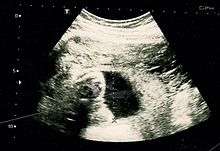

Suspicion of an abdominal pregnancy is raised when the baby's parts can be easily felt, or the lie is abnormal, the cervix is displaced, or there is failed induction of labor.[1] X-rays can be used to aid diagnosis.[12] Sonography can demonstrate that the pregnancy is outside an empty uterus, there is reduced to no amniotic fluid between the placenta and the fetus, no uterine wall surrounding the fetus, fetal parts are close to the abdominal wall, the fetus has an abnormal lie, the placenta looks abnormal and there is free fluid in the abdomen.[9][18] MRI has also been used with success to diagnose abdominal pregnancy and plan for surgery.[17][19] Elevated alpha-fetoprotein levels are another clue of the presence of an abdominal pregnancy.[20] Keyhole (laparoscopic surgery) can also be used to diagnose abdominal pregnancy[21]

Most cases can be diagnosed by ultrasound.[22] The diagnosis however may be missed with ultrasound depending on the operator's skill.[8][23]